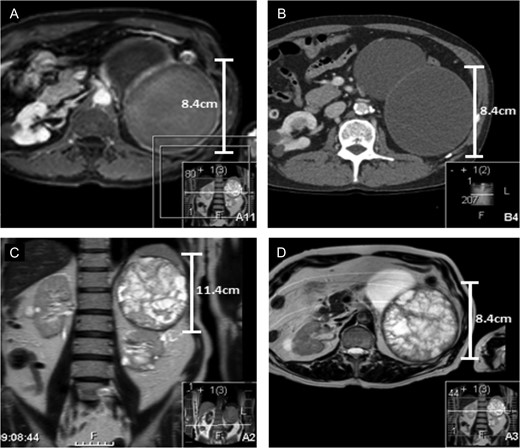

In 2014, the lower pole cyst in the left kidney had increased in size from 7.5 to 9.4 cm. A further 9.3 cm cyst had developed from the anterior midpole. The upper pole cyst had increased in size from 10.7 to 11.4 cm. The radiographic findings still indicated these cysts to be simple in nature. At this time the patient reported weight loss of 5 kg and fatigue over the last 6 months. eGFR had deteriorated to 29 ml/min. MRI corroborated CT results at this stage. MRI also demonstrated the left renal upper pole cyst to contain extensive thick walled septations. T1 gadolinium imaging demonstrated significant underlying haemorrhage. MRI findings upgraded the lesion from Bosniak IIF based on CT findings to Bosniak III. MRI and CT images illustrating these findings are outlined in Fig. 1.

(A and B) Represent contrast and non-contrast enhanced CT scans from 2014 of the left upper pole cyst when it was noted that the patient complained of 6 months of weight loss. The CT findings indicated the upper pole cyst to still be classified as Bosniak stage IIF. There is no notable calcification, septations or convincing solid components. (C and D) Both represent the MRI of the upper pole cyst. The findings images demonstrate extensive, thick septations in the upper pole cyst upgrading the cyst to Bosniak stage III. The scans outline the limitations of surveillance CT vs MRI to stage the severity of renal cystic disease in this patient.